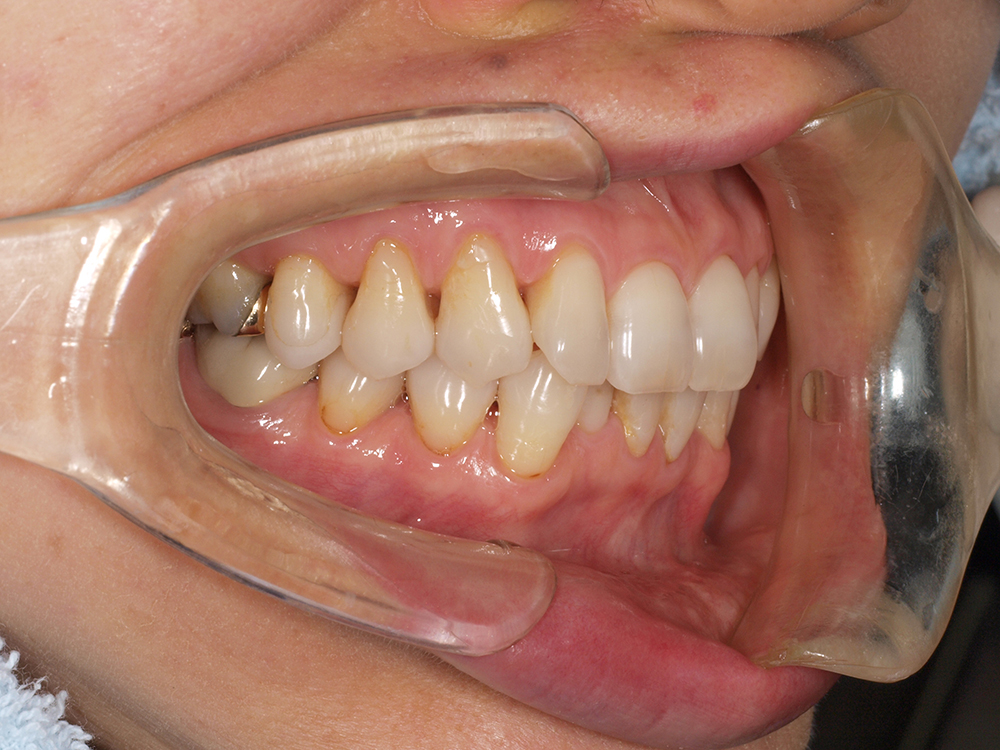

53歳 男性

- 主訴

- 全然噛めない。上の歯が取れてきた

- 処置内容

- 上顎:8本 下顎:2本

- 治療費用

- 上顎:約320万円(税込)、下顎:約160万円(税込)

- 治療期間

-

上顎:1年(仮歯まで8か月)

下顎:8か月(仮歯まで5か月)

- リスク

- 上部構造物、仮歯の破折、術後の腫れ(3日)、人工歯根脱落リスクがあります